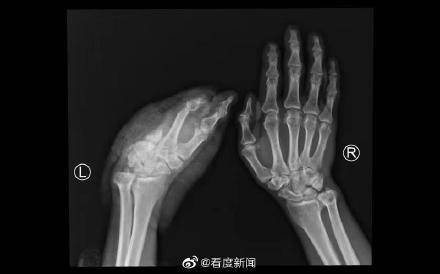

【四川运用疫苗冷链技术成功实施断掌再植手术】8月9日下午 , 患者为因车祸伤导致左手掌完全离断 , 因当地医院无再植医疗条件 , 经过初步处理后 , 采用疫苗冷链箱保存离断肢体 , 患者搭乘飞机于8月10日下午到四川省人民医院骨科急诊入院 。

一般断肢再植的最佳时机是伤后6-8小时 , 而该患者来院时离断肢体缺血时间已经超过24小时 , 且车祸伤导致的残端不规则 , 再植手术难度大 , 术后出现并发症的风险高 。 骨科肖成伟博士团队请示骨科胡豇主任 , 开展科内讨论后 , 决定冒着风险 , 做一次尝试性再植 , 给患者一次机会 。

经过积极的术前准备 , 在麻醉手术中心等相关科室的支持下 , 肖成伟博士团队很快开始了急诊再植手术 。 经过显微镜下长达6个半小时的奋战 , 一共吻合重建了3根动脉 , 6根静脉 , 5根神经 , 14根肌腱 。 8月11日凌晨2点 , 患者离断肢体恢复血供 , 再植手术获得初步成功 。